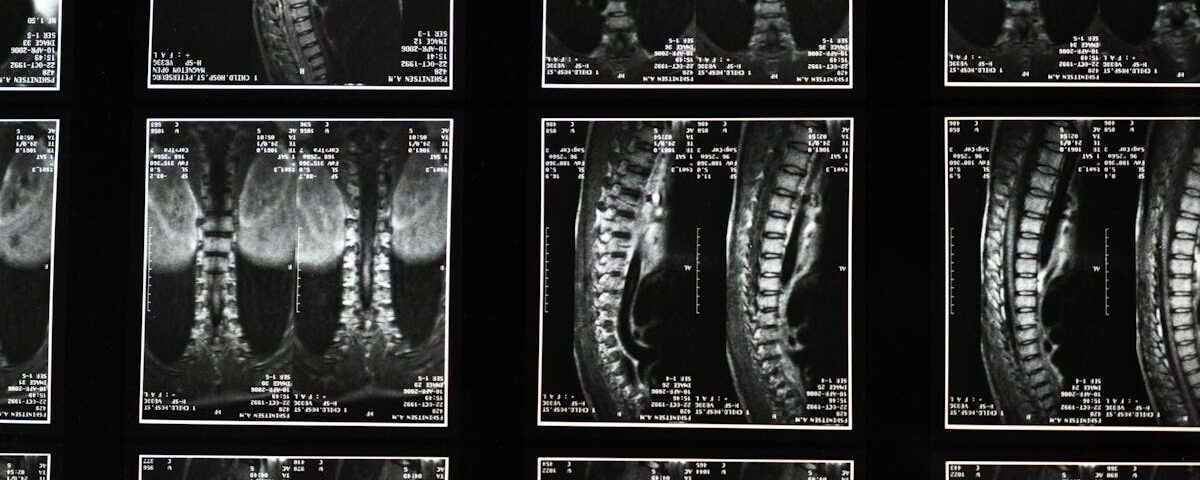

La hernie discale est une affection courante qui touche de nombreuses personnes, causant des douleurs intenses. Elle survient lorsque le noyau gélatineux d’un disque intervertébral fait saillie à travers une déchirure dans l’anneau fibreux. Cette pathologie peut entraîner une pression sur les nerfs voisins, provoquant des douleurs irradiantes, des engourdissements ou une faiblesse musculaire. Afin de traiter cette condition, la décompression spinale est souvent proposée comme une option non invasive efficace.

La décompression spinale est une technique qui vise à soulager la pression sur les disques intervertébraux en créant de l’espace entre les vertèbres. Cela se fait généralement à l’aide d’un appareil de traction qui permet d’étirer doucement la colonne vertébrale. La création de cet espace peut faciliter le mouvement du noyau du disque, aidant ainsi à réduire la douleur et à favoriser la guérison. Cette approche présente plusieurs avantages qui en font un choix privilégié pour le traitement des hernies discales.